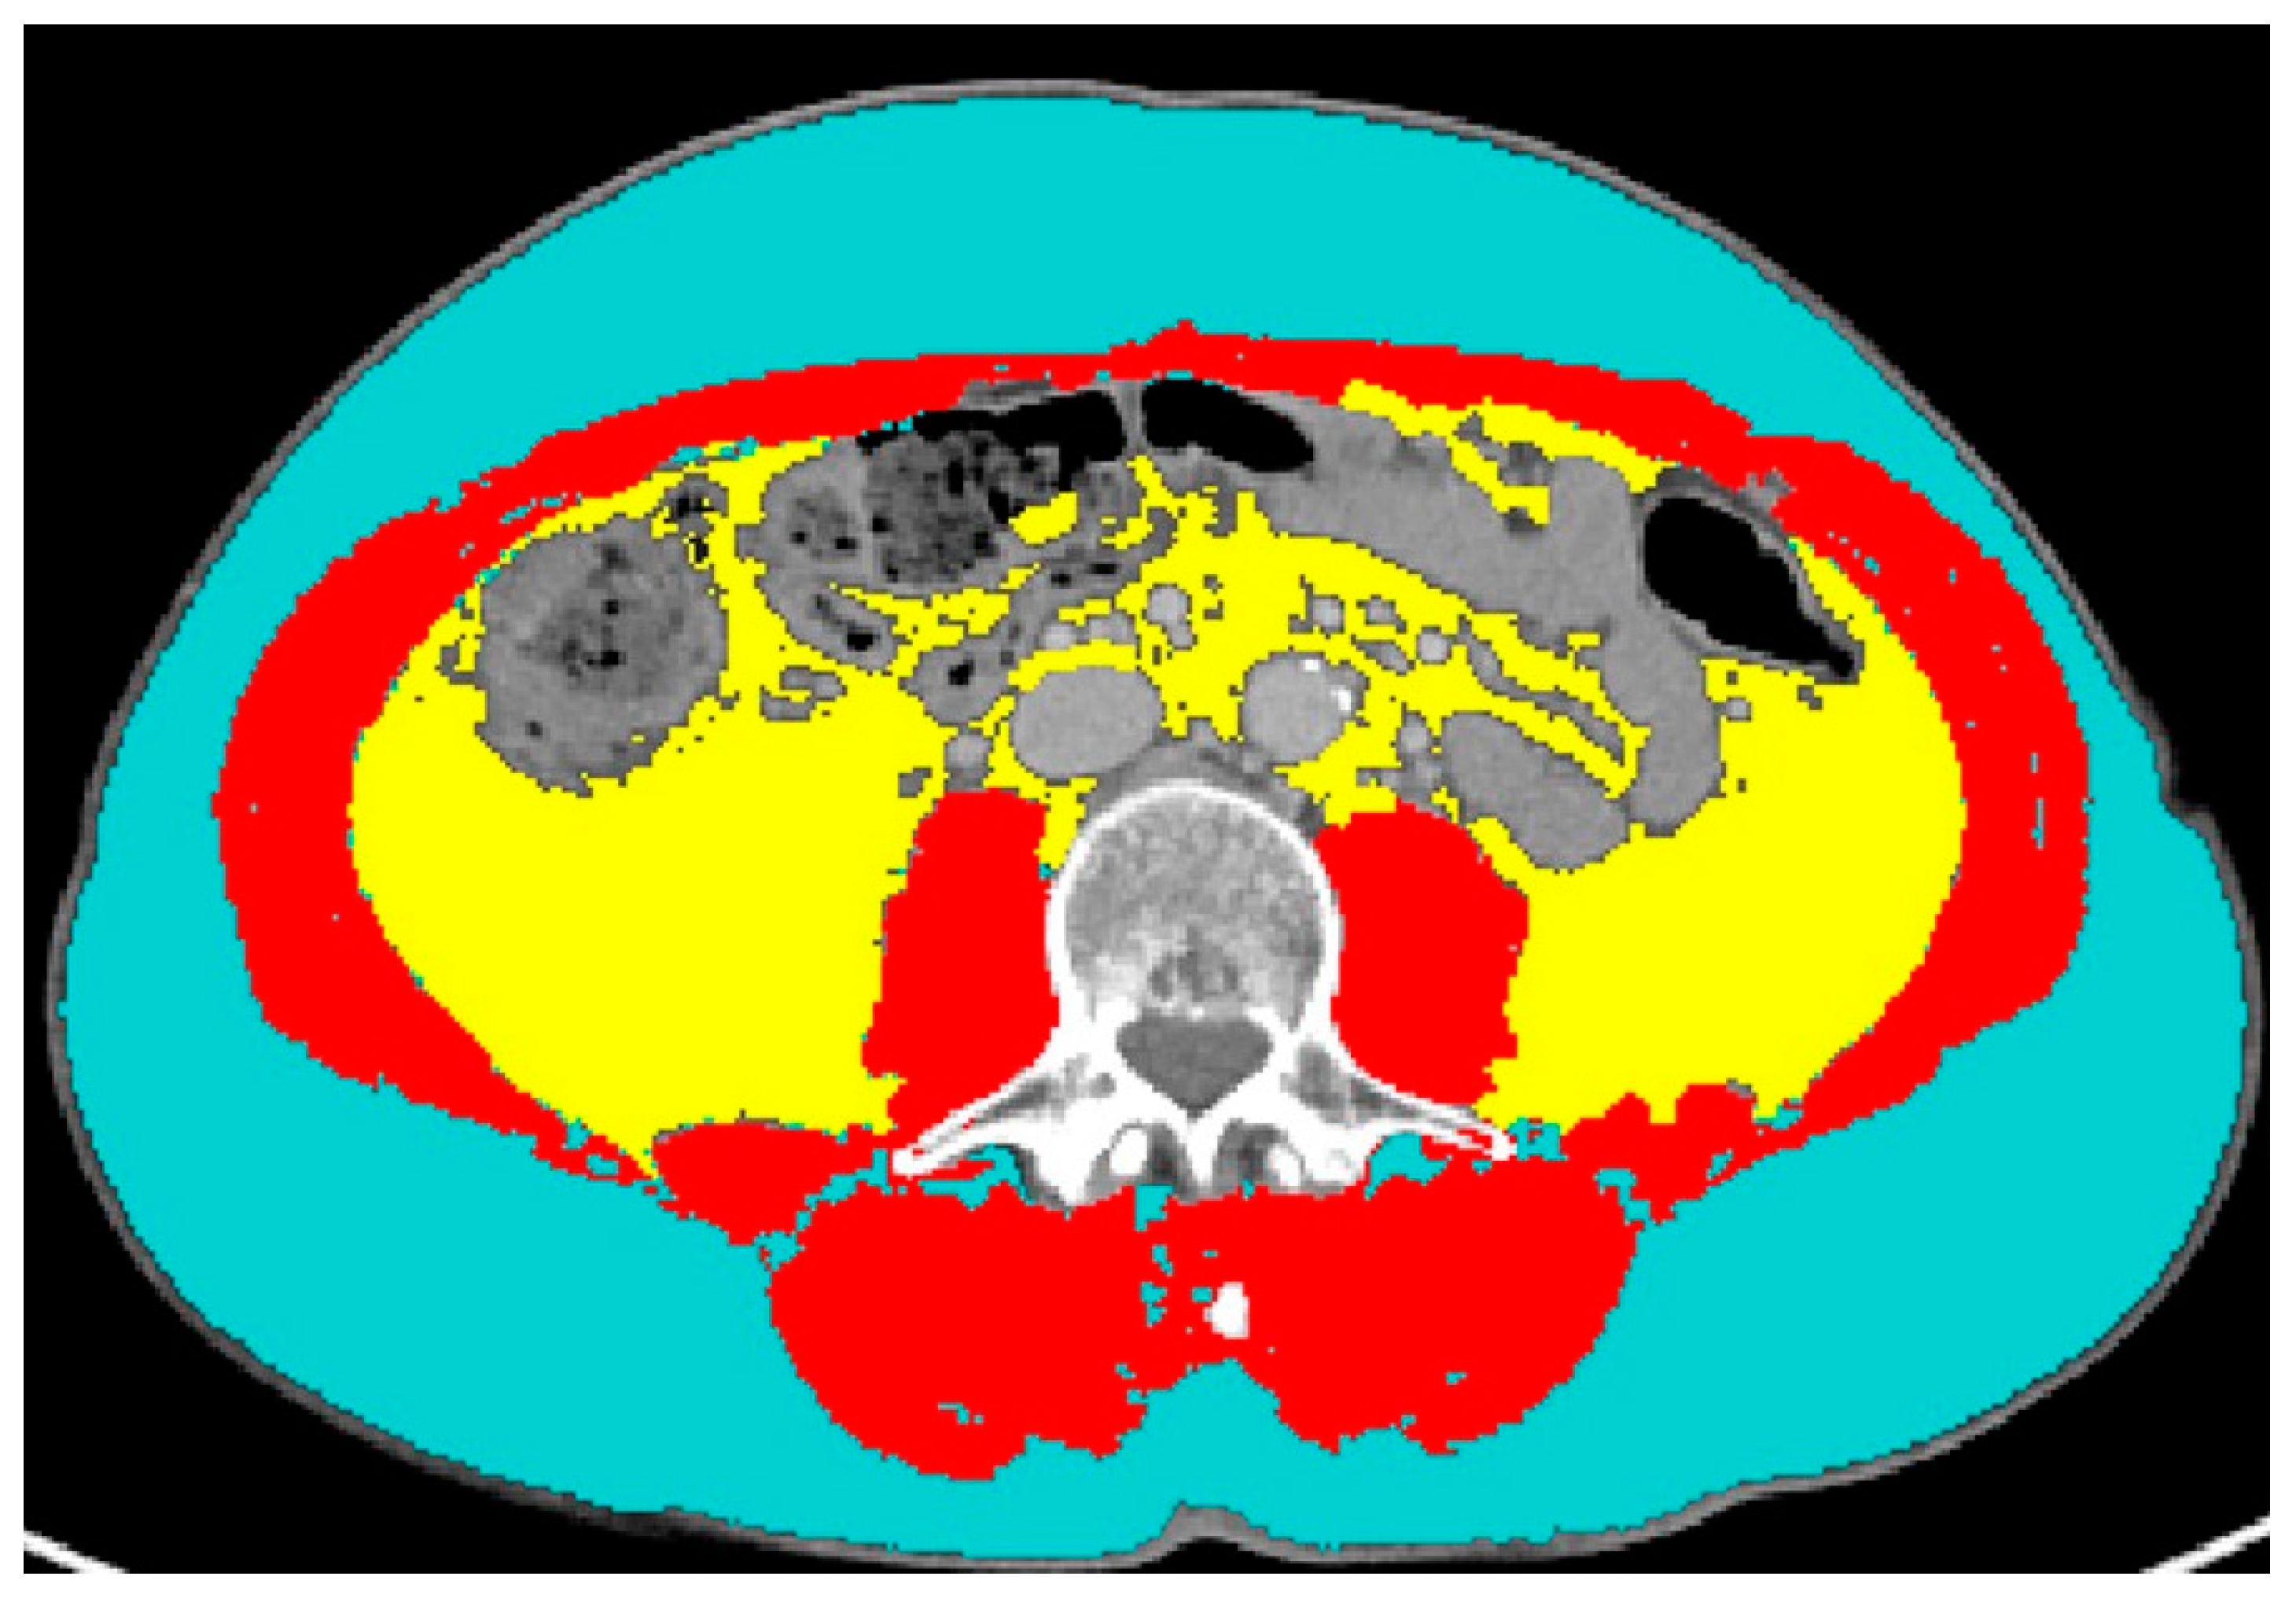

2.3. CT Data Extraction